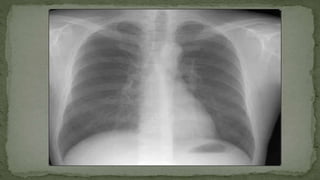

 Part – A (Chest X-ray Basics)

 Part – C (Chest X-ray Pathology)

CHEST X-RAY BASICS

CHEST X-RAY PHYSIOLOGY

CHEST X-RAY PATHOLOGY